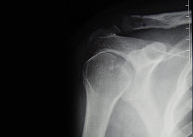

Las luxaciones acromioclaviculares son producidas por traumatismos en el hombro y producen la separación entre la clavícula y el acromion. La fuerza deformante puede llegar al hombro de forma directa (impacto sobre el hombro) o de forma indirecta tras caída sobre la mano con la extremidad extendida y transmisión del impacto al hombro.

En función de la separación entre los huesos que forman la articulación (acromion y clavícula) el tratamiento puede ser conservador o quirúrgico. Cuando la separación es grande y la posibilidad de restauración por métodos conservadores es imposible proponemos una rápida y mínima intervención para la reparación articular definitiva